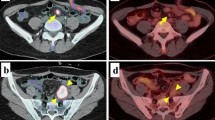

In patients with normal renal function, topotecan is mainly eliminated by renal excretion, with approximately half of the administered intravenous dose excreted as parent drug in the urine [10]. Recently, pharmacokinetic studies in patients with impaired renal function showed that reduction of topotecan dosages in patients from 1.5 to 0.75 mg/m2 resulted in adequate topotecan levels [11]. Moreover, topotecan was successfully administered in an anephric child at a dose of 0.75 mg/m2 for 5 days in 30 min, with hemodialysis on the second day and fourth day [13]. It was shown that topotecan disposition was minimally affected by hemodialysis and was similar to that observed in children with Wilms tumor, without renal failure. Likewise, in our patient who was on peritoneal dialysis, the levels of topotecan in plasma, after the administration of a reduced dose, were comparable to the pharmacokinetic data of a previously described anephric child [13]. As shown in Fig. 2a and Table 1, topotecan pharmacokinetics on day 1 and day 5 are comparable, illustrated by the minimal increases in the trough levels before start of the infusion. During the infusion, topotecan concentrations in peritoneal dialysate were lower than those observed in plasma, while peak concentrations in the dialysate were reached 1–4 h after the end of infusion (Fig. 2b). This is consistent with an earlier publication in which it was shown that both pleural and ascites represents only a small additional compartment for topotecan distribution [6]. Although topotecan is eliminated by peritoneal dialysis, as shown here, peritoneal dialysis is less effective than by the kidneys for the clearance of the drug. Dose reductions of topotecan in patients on peritoneal dialysis are thus required.

Fig. 2

figure 2

a Pharmacokinetic profile of topotecan total concentration in plasma (days 1–5). b Pharmacokinetic profile of topotecan total concentration in peritoneal dialysate (day 1 closed symbols, day 5 open symbols)